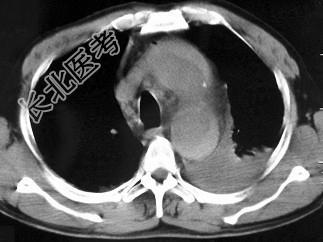

- 单项选择题男,58岁, 有高血压病史,突发胸背剧痛, CT扫描如图,其最可能的诊断为 ( )

E、主动脉夹层动脉瘤